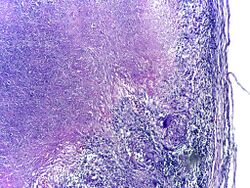

Microscopy of tuberculous epididymitis. H&E stain